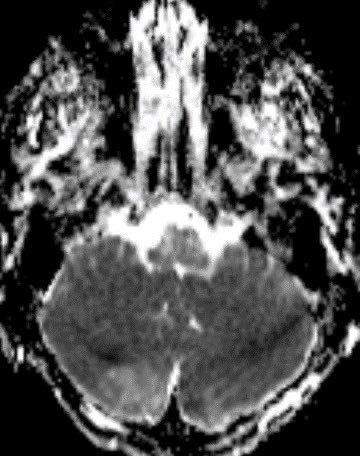

💡 Hypercellular tumor so DENSE on CT and DIFFUSION RESTRICTION (consistent feature)

Typically there is no to little enhancement and high signal on DWI due to T2 shine-through w/ high signal on ADC x.com

💡 Both Lhermitte-Duclos & Medulloblastoma SHH can have a striated appearance! Use DWI/ADC, density on CT, & enhancement to distinguish!